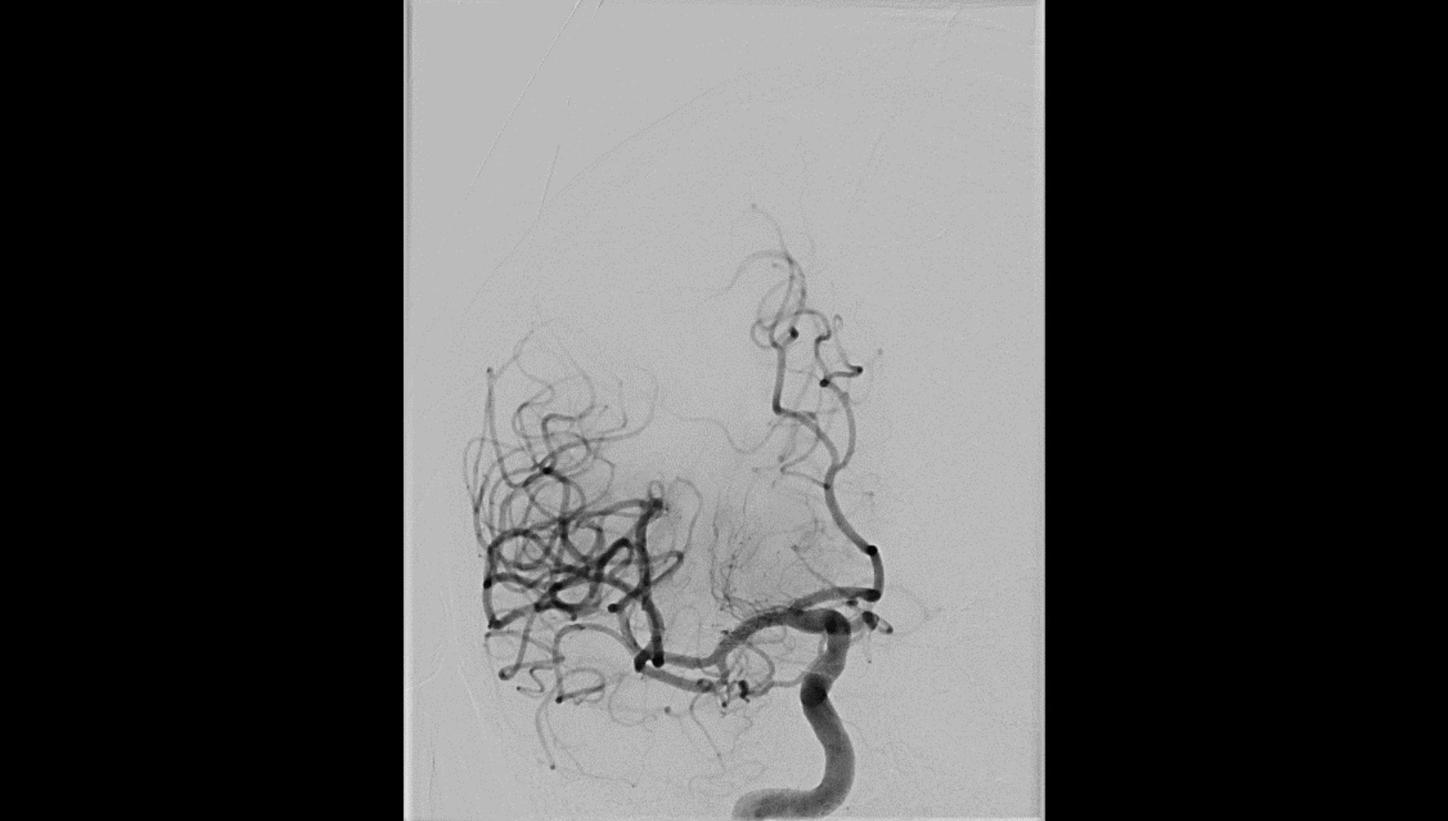

AP projection

AP projection Lateral projection

Lateral projectionFollow-up DSA to visualize treatment success

AP projection

AP projection Lateral projection

Lateral projectionFollow-up DSA to visualize treatment success

AP projection

AP projection Lateral projection

Lateral projection

In recent years, various clinical trials have shown the advantages of performing endovascular thrombectomy in patients with a high stroke score as well as of one-stop stroke care.

In their study, M. Psychogios et al. have shown that diagnosing and treating potential LVO patients on one system can save valuable time and significantly improve functional outcome.6